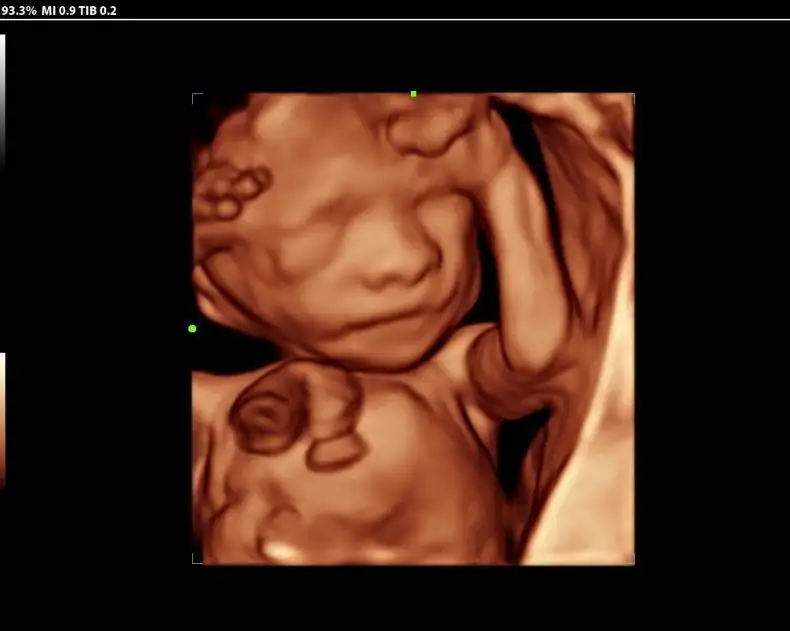

SonoDBaby 3D/4D/5D Imaging

Experience the magic of seeing your baby before birth with SonoDBaby, our dedicated 3D/4D/5D HD ultrasound service. At SDB Ultrasound Services, we offer a personalized, joyful, and comfortable experience for expectant parents wanting to bond with their baby and capture precios moments in stunning detail.

- 3D Ultrasound: Still, lifelike images of your baby’s face and body

- 4D Ultrasound: Real-time video of your baby moving, yawning, or smiling

- 5D HD Live Ultrasound: Enhanced clarity, lighting, and realism with true-to-life images